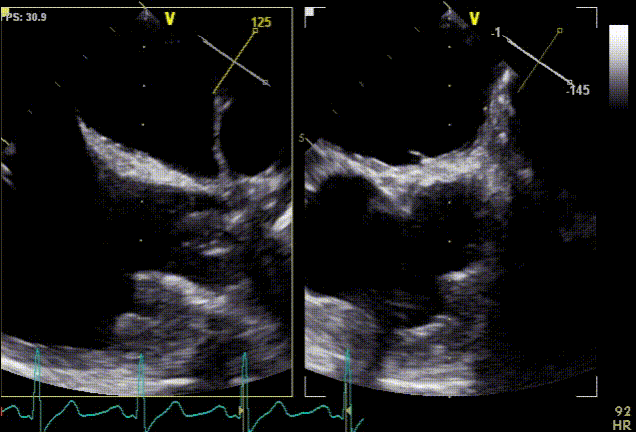

Suverénní diagnostickou metodou síňových trombů je jícnová echokardiografie. Alternativou je srdeční magnetická rezonance a CT, avšak právě výpočetní tomografie s sebou nese limitace ve formě nedostatečné distribuce kontrastní látky v oblastech krevní stázy. Následující kazuistika pojednává právě o nálezu izolované trombózy pravé aurikuly srdeční u pacienta po multimodální léčbě maligního mezoteliomu. Trombus byl diagnostikován jako vedlejší nález při PET/CT a následně potvrzen jícnovou echokardiografií.